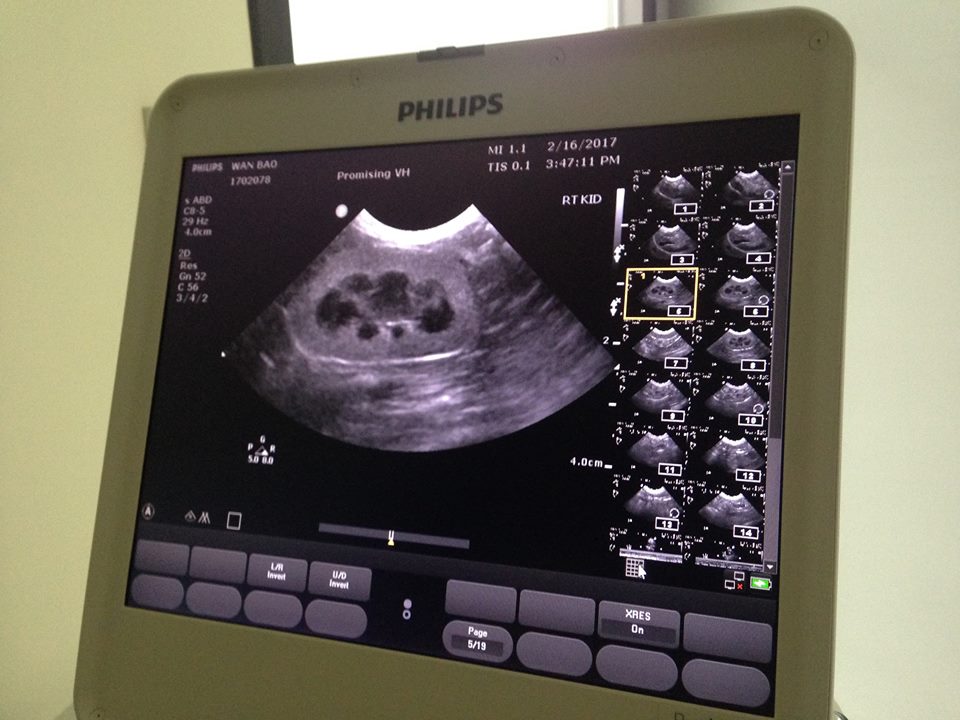

2/16澄諾回診-旺寶

【健檢狀況】

今日有做x光、血液及超音波的檢查,推測為6-8歲

收縮後的心肌為0.5不算太厚

但心雜音較大,建議到專心動物醫院做詳盡檢查

腎臟的皮質層很厚日後腎衰機率較高

肝、膽囊及胃黏膜的厚度看起來無大礙

腸子部分有很多的脹氣

所以針對嘔吐部分醫師認為腸子的影響比上消化道較高

所以先處理腸子脹氣的症狀